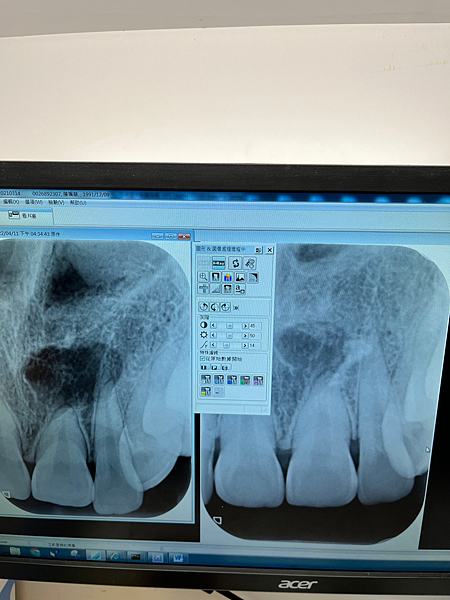

照X光發現我的上顎有個多生牙,我必須先轉診到別的地方拔除,以免矯正的時候傷到原本牙齒的牙根

2022/04/11 於國泰醫院-林宏政醫師,拔除多生牙

嗚嗚超級痛,局部麻醉針的有夠可怕,我的牙齒上在偏內側的地方,來來回回照了許多次X光

自費2400,可怕的是第一次拔除後已縫合,再去照X光發現還有殘留一點點很靠近骨頭的牙齒,於是又再次補麻醉拆線再磨一次,來來回回應該2個小時左右才拔乾淨我的牙齒